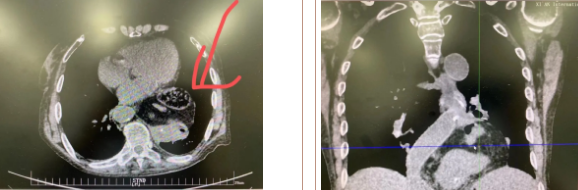

經(jīng)過三周充分準(zhǔn)備、院內(nèi)多學(xué)科會(huì)診及嚴(yán)謹(jǐn)?shù)男g(shù)前討論,西安國(guó)際醫(yī)學(xué)中心醫(yī)院胸科醫(yī)院李文海副院長(zhǎng)帶領(lǐng)團(tuán)隊(duì)為一位82歲高齡,多臟器功能不全且合并腫瘤患者成功實(shí)施“巨大膈疝修補(bǔ) 抗返流手術(shù)”。

據(jù)了解,患者多年來進(jìn)食后出現(xiàn)惡心、嘔吐,卻未到醫(yī)院進(jìn)行檢查。3個(gè)月前患者突然出現(xiàn)無尿,全身腫脹等情況才前往就醫(yī),卻遭多家醫(yī)院拒收,輾轉(zhuǎn)來到我院就診。檢查發(fā)現(xiàn)患者已患宮頸癌、進(jìn)而引起腎后性腎衰、同時(shí)合并膈疝、出現(xiàn)泌尿道感染,病情及其復(fù)雜。

經(jīng)泌尿外科積極救治,患者腎衰癥狀緩解,隨后轉(zhuǎn)入放射治療中心進(jìn)行宮頸癌根治性放療。放療期間,患者惡心、嘔吐癥狀逐漸加重,后期無法進(jìn)食,排除機(jī)械性腸梗阻和放療因素,考慮因長(zhǎng)期膈疝加重引起,經(jīng)胸外科會(huì)診后轉(zhuǎn)入胸外科一病區(qū)準(zhǔn)備手術(shù)治療。

麻醉手術(shù)中心副主任丁倩為減輕患者術(shù)后不適,實(shí)施單腔聯(lián)合支氣管封堵插管,同時(shí)進(jìn)行了肋間神經(jīng)阻滯麻醉。術(shù)中發(fā)現(xiàn)患者膈疝巨大,食管和疝囊分界不清,部分胃組織和結(jié)腸疝已進(jìn)入胸腔。李文海憑借豐富的臨床經(jīng)驗(yàn),仔細(xì)辨別解剖變異,有序完成分離、縫合、修補(bǔ)等一系列操作,胸外科穆強(qiáng)副主任醫(yī)師、劉歡住院醫(yī)師、麻醉手術(shù)中心團(tuán)隊(duì)通力配合,手術(shù)最終順利完成,患者安全返回胸外科監(jiān)護(hù)室病房。目前患者術(shù)后恢復(fù)良好,于近日準(zhǔn)備出院。